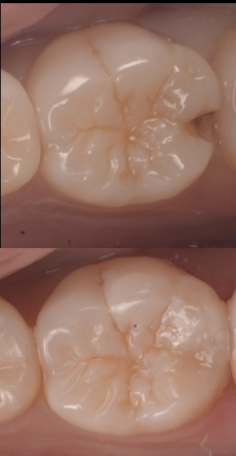

医院ブログ2025.10.14

【池袋】この歯、残せる?──抜歯と診断された歯を...